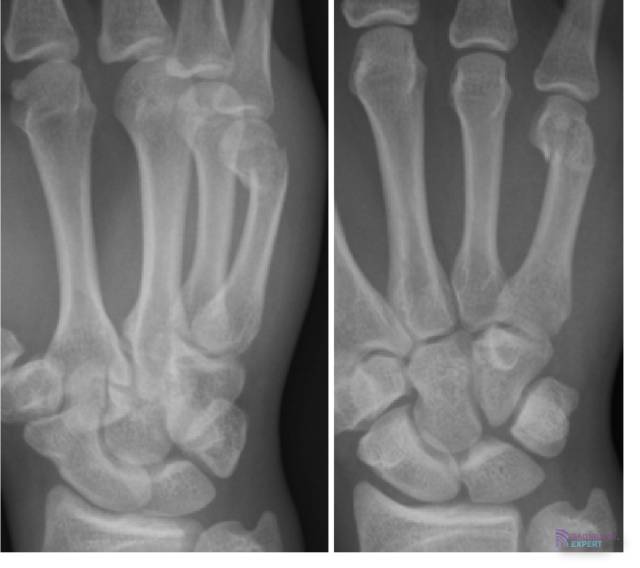

Subcapitaal fractuur MC-V (= boksersfractuur). Subcapitaal fractuur MC-V (= boksersfractuur).

Klik op afbeelding om overlay te zien